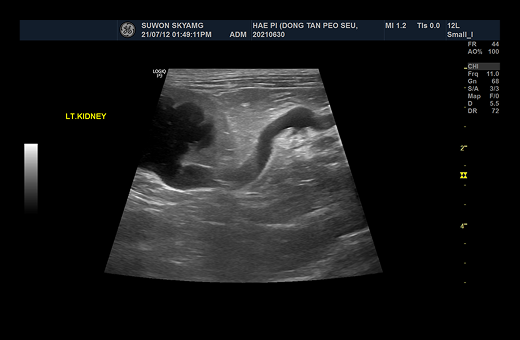

1-1 1-2

요관 확장으로 인해 SUB 수술적 치료 진행

2-1 2-2

요관 내에 결석 여러 개 관찰된 모습

· 초음파 검사

초음파 검사를 통해서 요관의 확장 정도와, 결석의 위치 등에 대한 정보를 확인하게 되며, 이로 인한 폐색에 따른 신우 확장 정도를 평가하게 됩니다. 신우 확장이 명확하고, 결석의 위치 정보 등이 확인되면, 수술적인 치료를 통한 폐색의 해소를 목표하게 됩니다.